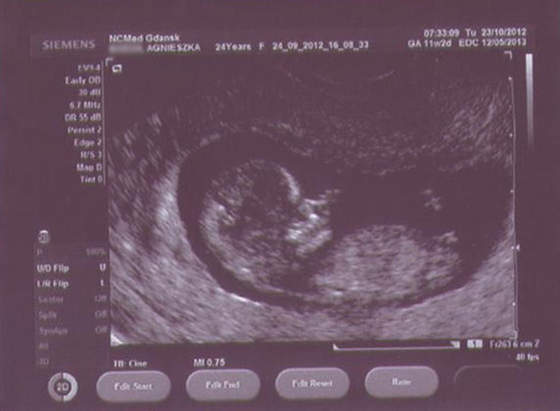

Pierwiosnek Pimpi Bimpi kręci się, wierci, nogami rozpycha i łapkami macha, pływa jak rybka, we wszystkich możliwych kierunkach, jednym słowem (właściwie dwoma) Dzidziul Wiercipięta. Chryste, w gardle mnie ścisnęło ze wzruszenia! Doktor mówi o nim per "Dzidziuś" (ZAWSZE!).

Dzidziulek zmierzony (4,76 cm). Tętno 160/min. Wg USG spodziewany termin porodu 7 maja, wg daty OM - 12 maja (trzeba zmienić datę, muszę napisać do Biedroneczki). Przezierność karkowa w porządku - 0,8 mm, nosek i wszystko co trzeba, też w porządku. Z TYM ŻE doktor powiedział, że COŚ TAM maleńkiego WIDAĆ między nogami (gdy zapytałam!), ale to o niczym nie świadczy, więc absolutnie nie możemy się tym sugerować (CHCĘ CÓRECZKĘĘĘĘĘĘĘĘĘĘĘ!!!). Aaaaaa, no i serduszko słyszałam - ale wypas!

A oto Pierwiosnek - dostałam 9 fotek, wybrałam dla Was 2 najbardziej widoczne